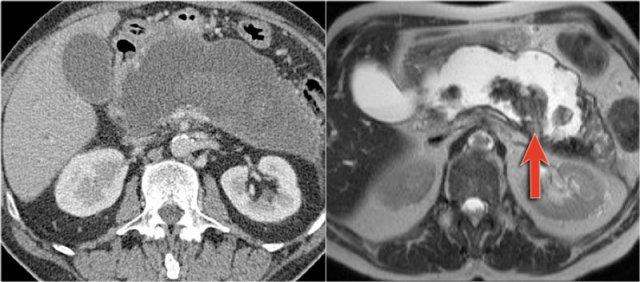

MRI cho thấy một tổn thương bao gồm nhiều nang nhỏ.

Đây có thể là u nang thanh dịch hoặc IPMN nhánh ống.

Sự thông thương của tổn thương nang với ống tụy cho thấy đây là IPMN nhánh ống.